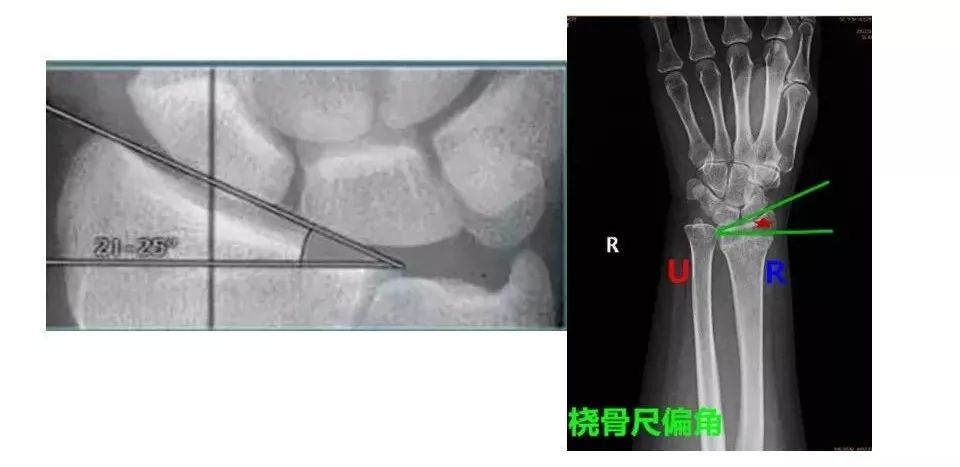

桡骨尺偏角桡骨掌倾角是指在腕关节侧位片中,桡骨远端关节面掌,背侧最

而正常状态下的桡骨下端关节面呈由背侧向掌侧,由桡侧向尺侧的凹面